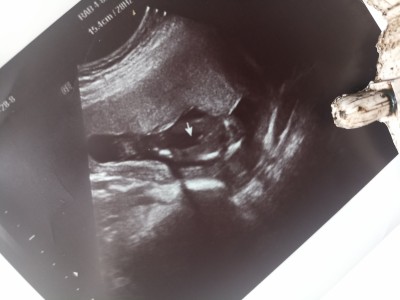

Şuan düşük tehlikem var dün kanamayla gittik doktor öncesinde erkek dedi ama kordon da olabilir dedi dün erkek bu dedi. Size de sormak istedim

Pipi canım benim oğlumun da böyle bir ultrason resmi var

Benim oğlanında ultrasonda böyleydi. Evet erkek bebek bu

Evet cnm erkek Bnm kızında tam böle yakaladık boştu ora ve kızım oldu seninki erkek

Kordon gibi  geldi canım renklide baksa anlardı aslında kordon olunca kan akışı çok yoğun oluyor renginden belli yoluyor.aslinda rabbim isağlıkla kucağına aldırsın inşallah

Pipi evet nerde gorsem tanirim bunu